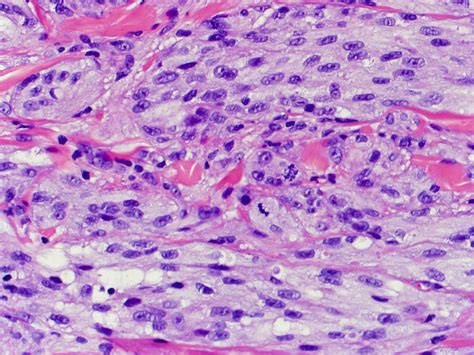

The histopathological features of granular cell tumours are distinctive and play a crucial role in their diagnosis. Key features include:

• Large, polygonal cells with abundant granular cytoplasm

• Small, centrally located nuclei

• Abundant lysosomes within the cytoplasm

• Positive staining for S-100 protein, a marker for neural and melanocytic differentiation

These features help differentiate GCTs from other types of tumours, such as rhabdomyomas and alveolar soft part sarcomas, which may have a similar appearance but different clinical behaviours.